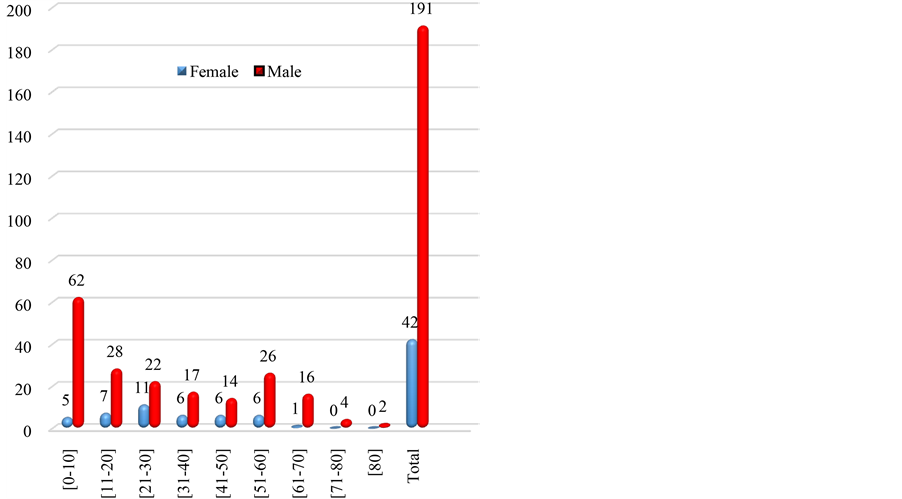

Figure 4. Distribution of patients according to age groups and sex.

The average age of patients was 36 years, ranging from 15 months to 88 years. With a staff of 67 cases or 28.77% of urolithiasis, the age group 0 - 10 years is the most represented, followed by 11 - 20 years and 51 - 60 years (Table 1). Youth 0 - 20 years are most frequently holders of secondary urethral calculi to complications of circumcision. Table 2, Figures 1-3 show the relationship between age and location of the stones. For each age group, the male patients were significant with a sex ratio of 4.5. The distribution by age and sex also shows a male predominance (Figure 4). The socioeconomic level seems to be a predisposing factor to the development of urolithiasis (n = 122 or 52.36%). The stones affected: school students and university students (n = 64 or 27.47%), non-professionals (n = 40 or 17.17%) and middle public officials (n = 36 or 15.45%). The water from traditional wells was used by 91 patients, 110 patients consumed less than one liter of water. Figure 5 reports the different reasons for consultation. Urolithiasis (n = 17) and urogenital bilharzia (n = 11) were found as medical history. The patients diet was rich in meat (n = 200), milk (n = 160), fish (n = 150) and eggs (n = 130).